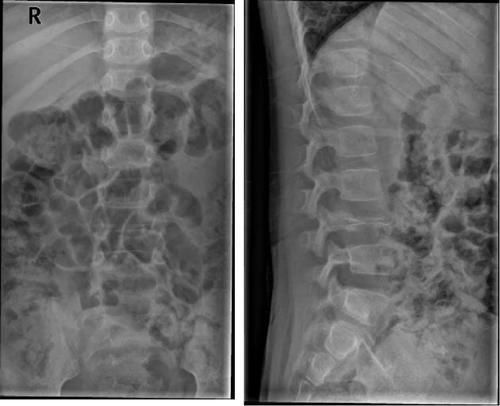

Case12:F,4y;患儿颈部活动受限1个月。

Case13:F,4y;腰痛1月余,加重半月。

文章插图